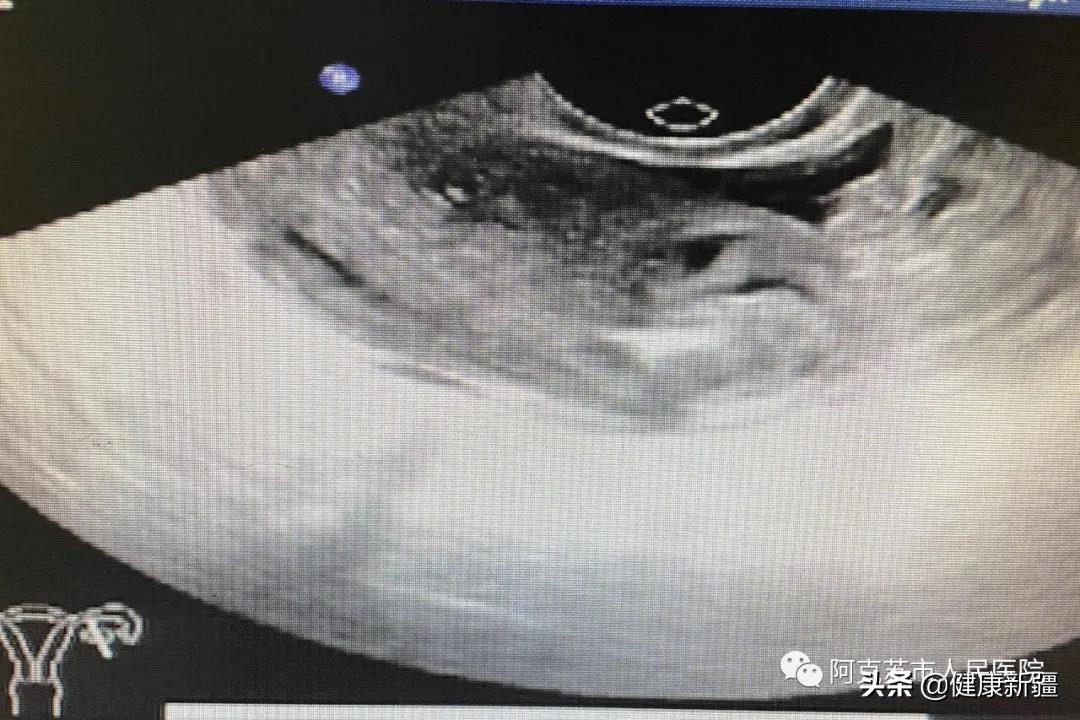

手术中

结合患者自身情况,经过反复沟通论证,研判宫外孕大小、位置、穿刺进针角度等指标,结合患者血hcg数值情况,超声科主任苏进元,副主任援疆专家张林,妇科主任刑庆玲建议为患者实行异位妊娠超声引导下介入治疗。